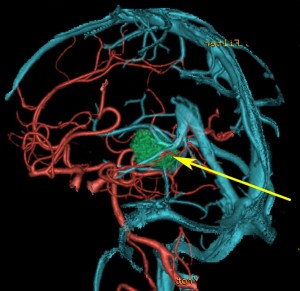

松果体腫瘍へのOTAのルートです。occipital transtentorial apporachというのは黄色の矢印に沿ってガレン大静脈の下に入る方法であり,そこから松果体部を通って第3脳室内へ直線的な視野が展開します。

一方,赤の矢印に沿ったルートは parieto-occipital transtentorial approachです。このルートでは内大脳静脈 internal cerebral veins を見ることがかなり難しいです。更に,第3脳室に入るためには脳梁膨大部 spleniumを切断する必用があります。ただし,小脳上部や第4脳室を見るときにはparietal寄りのルートを使います。

この2つのルートを混同している脳外科の先生はとても多いと思います。OTAとは,外後頭隆起を削除して,後頭極(後頭葉)を牽引して,テントの全長を切開しなければ遂行できない到達法であることを認識して下さい。